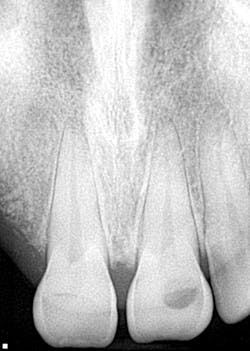

A healthy 31-year-old male reports that besides a visit to the dentist four years ago to have a bridge done on the upper right side, any previous dental visits occurred when he was around 14–15 years old. Upon initial examination with radiographs (by a previous dentist shortly after the accident), it was determined that the patient had caries on teeth nos. 8, 9, 12, 13, 15, and 30 with advanced, generalized class III periodontal disease. Interestingly enough, it was also determined that the patient was “totally temporarily disabled” for one week following his surgery and extractions. One week.

- Teeth nos. 14 and 15 both had supererupted into the 18 and 19 space (figure 2).

- There was positive spacing in the upper right/anterior quadrant, larger than the replacement of teeth nos. 6 and 7 would fill.

- Additional caries were noted on nos. 10, 11, 14, 26, 27, and 29—primarily facial/buccal caries (figures 3–8)